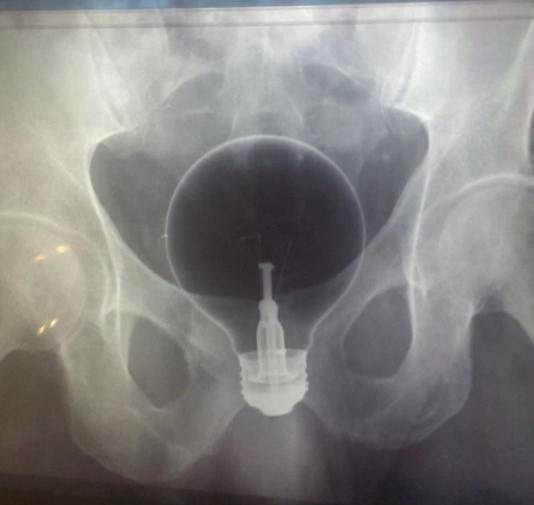

割れ物注意

肛門や膣にガラス製品を挿入すると、ちょっとした圧力で、体内で破損する恐れがあります。特に事故として事例が多いのは、電球やワイングラスです。比較的安全なのは、ビール瓶のような圧口で多きいものです。

こ、これは・・・・・・で、電球だあ!

レントゲンになっているということは病院で診察を受けたということね。危険を知らずに、入れてしまうと、とても恥ずかしい思いをすることになるわ。